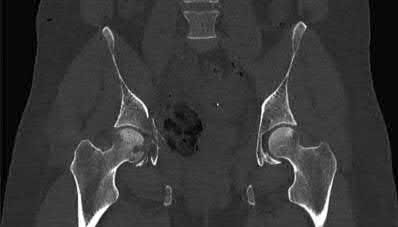

A 13-year-old obese male complains of left knee pain and a limp for 3 weeks. Radiographs are provided:

He is able to bear weight with crutches. During physical examination, as the affected hip is passively flexed, into which position will the limb obligately deviate?

Explanation

In slipped capital femoral epiphysis (SCFE), the proximal femoral epiphysis displaces posteriorly and inferiorly relative to the femoral neck. This altered anatomy leads to an obligate external rotation of the thigh during passive hip flexion, a classic physical examination finding.